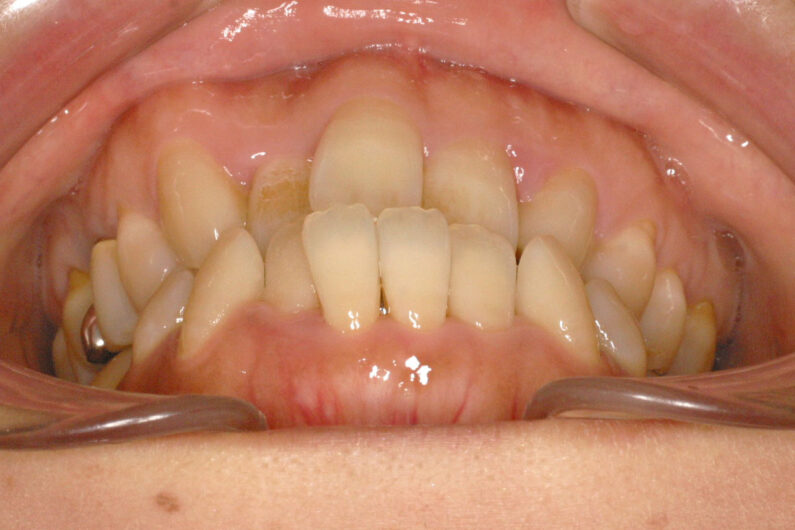

前歯部に叢生(がたつき)がある、受け口、前歯反対咬合の患者さんです。

虫歯の処置歯が多いだけでなく、左上の側切歯が欠如しており、上顎正中(歯並びの中心)が1歯分、左側にずれています。

前歯部の被蓋(咬み合わせ、重なり)と叢生の改善、上顎正中の右側移動を目的として、抜歯による治療を行いました。

マルチブラケット 動的治療期間 2年1か月 調整回数27回